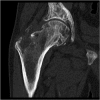

Gaucher disease (GD) is a rare, genetic lysosomal disorder leading to lipid accumulation and dysfunction in multiple organs. Involvement of the skeleton is one of the most prevalent aspects of GD and a major cause of pain, disability, and reduced quality of life. Uniform recommendations for contemporary evaluation and management are needed. To develop practical clinical recommendations, an international group of experienced physicians conducted a comprehensive review of 20 years' of the literature, defining terms according to pathophysiological understanding and pointing out best practice and unmet needs related to the skeletal features of this disorder. Abnormalities of bone modeling, reduced bone density, bone infarction, and plasma cell dyscrasias accompany the displacement of healthy adipocytes in adult marrow. Exposure to excess bioactive glycosphingolipids appears to affect hematopoiesis and the balance of osteoblast and osteoclast numbers and activity. Imbalance between bone formation and breakdown induces disordered trabecular and cortical bone modeling, cortical bone thinning, fragility fractures, and osteolytic lesions. Regular assessment of bone mineral density, marrow infiltration, the axial skeleton and searching for potential malignancy are recommended. MRI is valuable for monitoring skeletal involvement: It provides semiquantitative assessment of marrow infiltration and the degree of bone infarction. When MRI is not available, monitoring of painful acute bone crises and osteonecrosis by plain X-ray has limited value. In adult patients, we recommend DXA of the lumbar spine and left and right hips, with careful protocols designed to exclude focal disease; serial follow-up should be done using the same standardized instrument. Skeletal health may be improved by common measures, including adequate calcium and vitamin D and management of pain and orthopedic complications. Prompt initiation of specific therapy for GD is crucial to optimizing outcomes and preventing irreversible skeletal complications. Investing in safe, clinically useful, and better predictive methods for determining bone integrity and fracture risk remains a need. © 2019 The Authors. Journal of Bone and Mineral Research Published by Wiley Periodicals Inc.